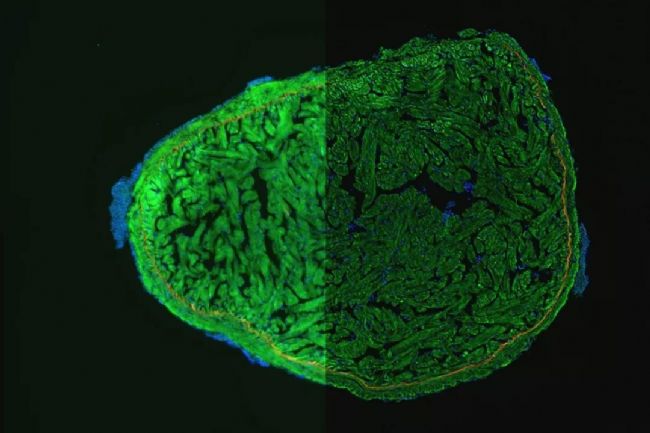

▲ 圖 10.斑馬魚心臟

藍色 DAPI:細胞核,紅色:心肌細胞原肌球蛋白,綠色 GFP:primordial cardiac layer

來自:Anna Jazwinska, 弗里堡大學,法國